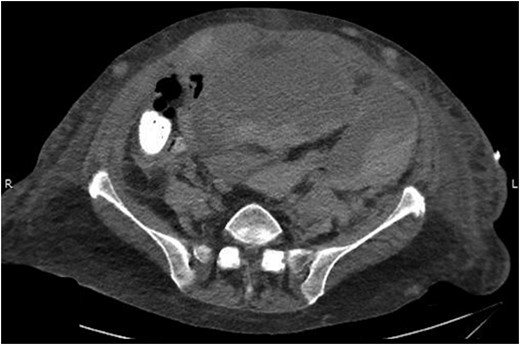

Her intra-abdominal bladder pressure (IAP) was noted to be 31 mm Hg (Grade IV intra-abdominal hypertension). The patient was emergently taken to the operating room (OR) for abdominal decompression. Necrotic rectus muscle was noted when the fascia was transected. Two liters of organized clot and blood was removed which had dissected into the retroperitoneal space bilaterally. After the damage control laparotomy, the patient was admitted to the surgical ICU with temporary abdominal wall closure achieved by application of Abthera™ ‘Vacuum Assisted Closure’ (KCI, San Antonio, TX, USA). Patient was taken back to the OR within 24 h for re-exploration and abdominal fascial closure. She recovered very well from her surgery with normalized bladder pressures and complete recovery of renal function. A repeat CT scan on postoperative Day 10 showed complete resolution of her rectus sheath and retroperitoneal hematomas (Fig. 3).

Abdominal CT scan showing complete resolution of rectus sheath and retroperitoneal hematomas.